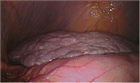

1. 肝硬変は慢性の炎症と肝細胞障害の結果であり、肝臓全体に線維化と線維化に伴う結節形成が解剖学的に認められる状態と定義され、慢性肝疾患の末期状態である。

1. 主な原因は肝炎ウイルスやアルコール摂取、脂肪肝などがある。近年、生活習慣に基づく脂肪性肝炎が増加しており、とくに若年女性での酒量増加が増えてきているため、今後注意が必要である。